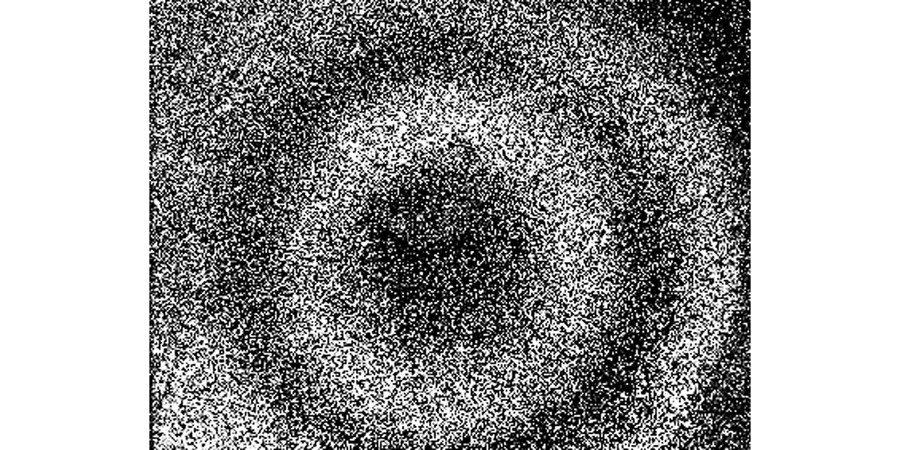

First, the theoretical analysis proves that using the spatial carrier phase extraction method to detect the amplitude distribution in eardrum samples in the vibration mode is reasonable. In the finite element simulation and experimental analysis, the vibration modes of the artificial eardrums with defects were analyzed, and the results showed that different defects affect the amplitude distribution in the first-order vibration mode for the eardrums differently. For the perforated eardrum samples, the amplitude distribution was analyzed by varying the size and location of the perforation. The results show that the amplitude near the perforation increases significantly with the increase in perforation size (Figs. 3 and 4), and an increase in the number of fringes is observed in the experimental results (Fig. 11). By changing the location of the perforation, the maximum amplitude shifts off-center with the perforation, and the larger the perforation, the more evident the deviation. The amplitude distribution for the scratched eardrum samples was analyzed by varying the size and location of the scratch. The results show that at the same location, the larger the scratch length, the larger the surface amplitude of the film (Fig. 5), and the amplitude changes more significantly near the scratch location (Fig. 6). The experimental results show an increase in the number of fringes, and the shape of the fringe near the central scratch is flat (Fig. 12). When the scratch is off-center, the effect on the amplitude near the scratch is significantly greater than that at the center. The amplitude distribution for the calcified eardrum samples was analyzed by varying the thickness of the calcified layer (Fig. 7). The amplitude of the film decreases with an increase in the thickness of the calcified layer but is more evident at the location of the calcified layer (Figs. 8 and 13).

根据上述仿真,用

实验样本与仿真时的样本保持一致,

图 11. 穿孔薄膜的一阶振动模态图。(a)中心穿孔3 mm薄膜;(b)中心穿孔5 mm薄膜;(c)偏心穿孔3 mm薄膜;(d)偏心穿孔5 mm薄膜

Fig. 11. First-order vibrational mode diagrams of perforated films. (a) Film with a 3 mm diameter perforation in the center; (b) film with a 5 mm diameter perforation in the center; (c) film with an eccentric 3 mm diameter perforation; (d) film with an eccentric 5 mm diameter perforation

针对上述的薄膜划伤仿真分析,同样进行了相应的实验验证,得到的中心划痕样本的一阶振动模态图如

图 12. 划伤薄膜的一阶振动模态图。(a)中心3 mm划伤薄膜;(b)中心6 mm划伤薄膜;(c)偏心3 mm划伤薄膜;(d)偏心6 mm划伤薄膜

Fig. 12. First-order vibrational mode diagrams of scratched films. (a) Film with a 3 mm scratch in the center; (b) film with a 6 mm scratch in the center; (c) film with an eccentric 3 mm scratch; (d) film with an eccentric 6 mm scratch